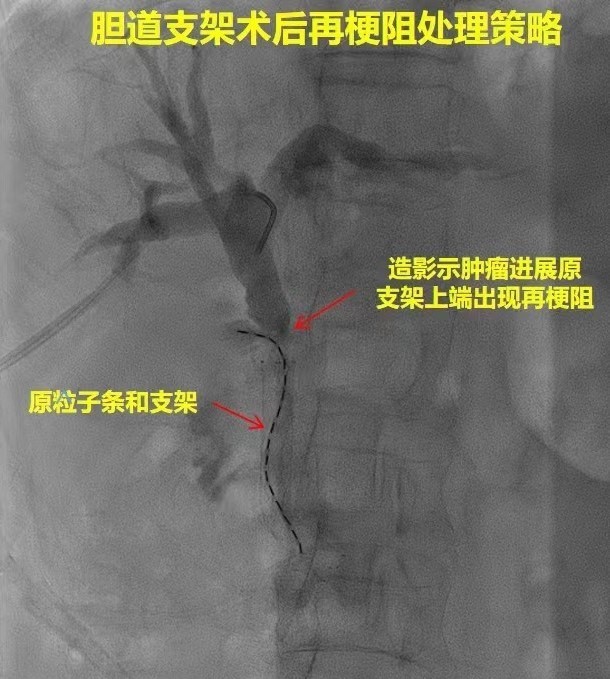

惡性腫瘤行膽道支架治療的缺點是支架由于腫瘤生長導(dǎo)致再梗阻,125I粒子腔內(nèi)治療可有效彌補(bǔ)。采用雙腔施源導(dǎo)管可控制腫瘤生長,半年后更換導(dǎo)管保證治療可延續(xù)性,現(xiàn)已有相關(guān)文章發(fā)表。

2017年11月蚌埠醫(yī)學(xué)院第一附屬醫(yī)院肝膽外科曾在中國微創(chuàng)外科雜志上發(fā)表,2012.6月--2016.3月對33例仍能耐受支架置入手術(shù)者,再次在數(shù)字減影血管造影下行經(jīng)皮經(jīng)肝膽道金屬支架置入。再次行經(jīng)皮膽道支架置入手術(shù)難度比首次操作大,經(jīng)PTCD管造影后置入導(dǎo)絲。拔出PTCD管鞘管置入后,置入造影導(dǎo)管與導(dǎo)絲配合通過梗阻部位導(dǎo)絲,必須通過支架頭端置入不能從上次支架的網(wǎng)眼通過,否則支架置入后不易自膨開從而影響減黃效果。導(dǎo)絲通過時由于支架的影響操作比首次困難,必要時可借助超細(xì)膽道鏡指引導(dǎo)絲的方向。對于經(jīng)皮經(jīng)肝膽道支架置入術(shù)后再次出現(xiàn)梗阻性黃疸者,再次行膽道支架置入術(shù)可一定程度延長生存期,改善生活質(zhì)量。總之對于支架梗阻者再次經(jīng)皮置入膽道支架可以改善肝功能,提高生存質(zhì)量并有可重復(fù)操作的優(yōu)點,安全性較高值得臨床應(yīng)用。